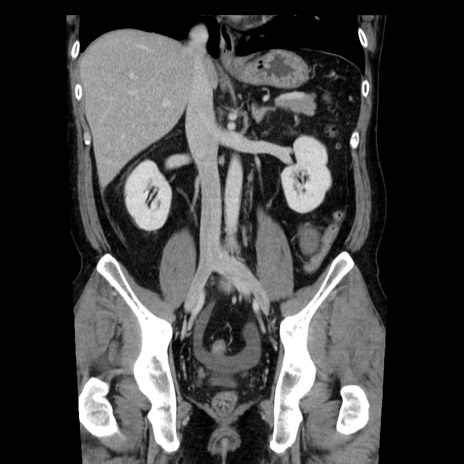

症例29(冠状断像)

【症例】40歳代男性

【現病歴】2日前から胃痛あり。徐々に周期的な激痛に変化した。本日になっても激痛があるため受診。

【身体所見】意識清明、BT 38-39℃台あり、腹部:膨満、やや硬、右下腹部に圧痛あり。

【データ】WBC 8500、CRP 23.26